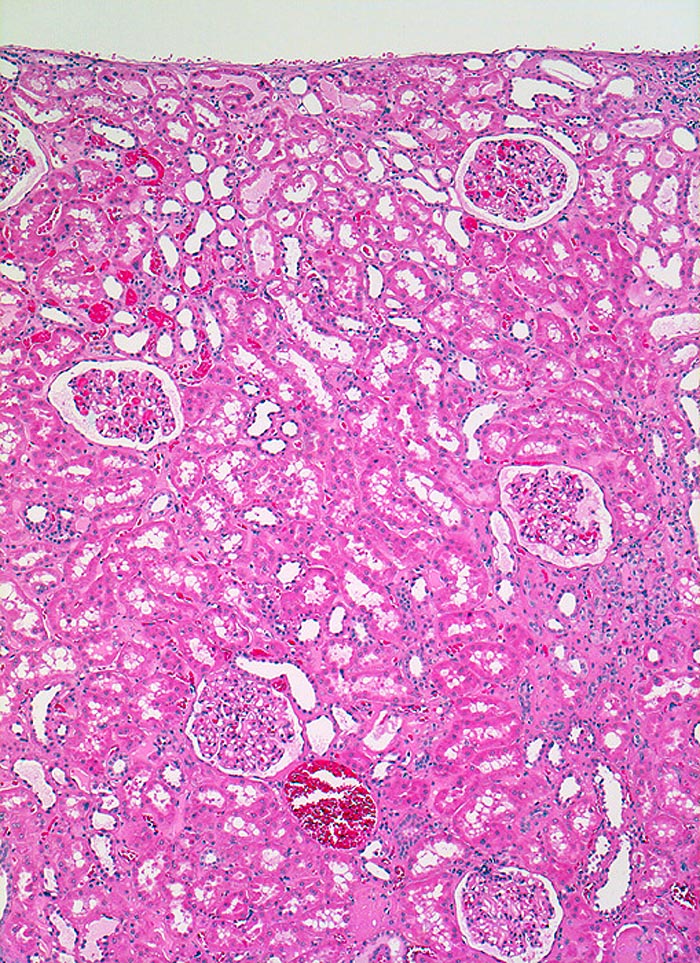

PathoPic ID 3441 - Normale Nierenrinde

Normale Nierenrinde

Normalbefund

Niere

Niere, Harnwege

Unauffällige Nierenrinde

Histologie

50